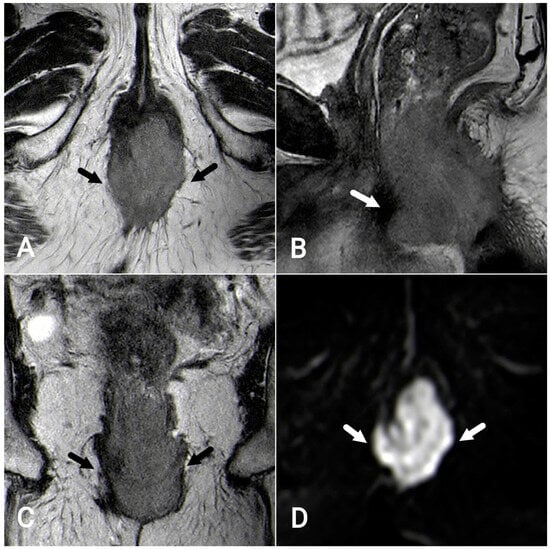

7.1. T-Staging

7.2. N-Staging

- Short-axis diameter ≥ 9 mm;

- Short-axis diameter 5–8 mm AND ≥2 morphologically suspicious characteristics *;

- Short-axis diameter < 5 mm AND 3 morphologically suspicious characteristics *;

- Mucinous lymph nodes (any size).

- Round shape;

- Irregular border;

- Heterogeneous signal.